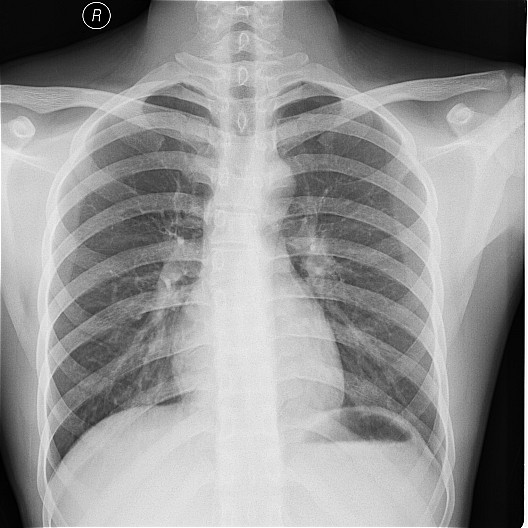

一钨矿工厂因有毒气体泄漏(据说是硝酸)造成十多名工人中毒,均出现不同程度的咳嗽,气逼,心跳加快等中毒症状.其中有几例患者胸片出现小点片状,结节状阴影.是此次中毒引起的肺部改变还是原来就患有矽肺病或其它病变.

肺水肿,及原来就患有矽肺病

原就有的矽肺,未见中毒性肺水肿

矽肺,部分胸片可见肺水肿。治疗复查